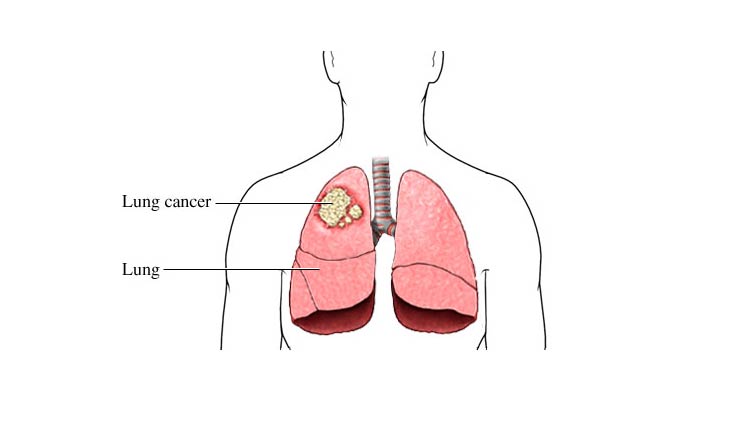

फेफड़े हमारे शरीर का एक महत्वपूर्ण अंग है जिसके बिना हमारा जीवित रहना असंभव है क्योंकि इसका काम हवा से ऑक्सीजन को अलग करके रक्त में पहुंचना होता है। हमारे शरीर से कार्बन डाईऑक्साइड पैदा होती है, जो फेफड़ों के द्वारा शरीर से आसानी से बाहर निकल जाती है। लेकिन कई बार हमारे शरीर में संक्रमण होने लगता है। जिसके कारण हमारे फेफड़े सही से काम नहीं करते और खराब होने लगते हैं। जो फेफड़े के कैंसर का रूप धारण कर लेते हैं।यह बीमारी आजकल बहुत ही ज्यादा बढ़ गयी है जिससे कई लोग ग्रसित होते है। यह समस्या पुरुष या महिला दोनों में से किसी को भी हो सकती है। तो आइये जानते है इसके लक्षण, कारण और बचाव के बारे में.....